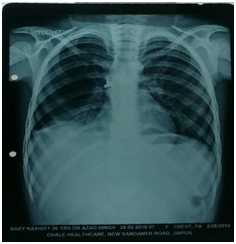

Case 2: A 5 year old girl reported to the hospital with history of chronic cough since 2 years; she had episodes of recurrent URTI. There was no history of FBA. She had been treated many times by physicians for acute bronchitis in this period and experienced temporary relief after medication. She had diminished chest movement on the right and dullness to percussion was elicited on the right as well. She had a markedly diminished breath sound over the right lung field. Chest X ray was advised which showed a radiopaque object lodged in the right main bronchus with resultant atelectasis of the entire left lung and compensatory emphysema of the right lung (Figure 1) Bronchoscopy revealed a black metallic stud in the right main bronchus. a mass of granulation tissue surrounded the body (Figure 3) (Figure 4) (Figure 5).

Radiographic examination is an invaluable asset in the diagnosis of an aspirated foreign body.20–22 In a radioopaque foreign body, examination is straightforward; when the foreign body is nonradiopaque, secondary changes such as atelectasis and obstructive emphysema are of diagnostic importance. The common radiological sign in our series was obstructive emphysema. A CT thorax is not frequently requested but this is indicated if there is high index of suspicion regarding chronic pulmonary changes due to the prolonged presence of FB.23